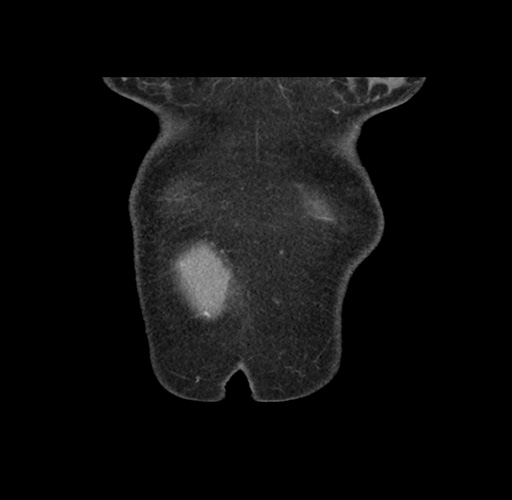

Imaging Analysis

Look through the patient's CT scan to identify any areas of concern for the necessary procedure.

Based on your CT findings, which issue(s) would give reason for "planned slowing down moment(s)" in this case?